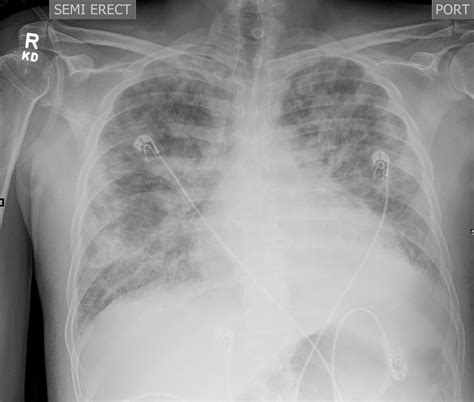

Diagnosis is primarily clinical, but imaging plays a vital role in confirming the extent of the spread. Computed Tomography (CT) scans are the gold standard for detecting subcutaneous gas and identifying the depth of the fascial involvement, which aids surgeons in planning the scope of the necessary debridement.

• Hemodynamic Resuscitation: Aggressive fluid resuscitation to combat septic shock and manage electrolyte imbalances.